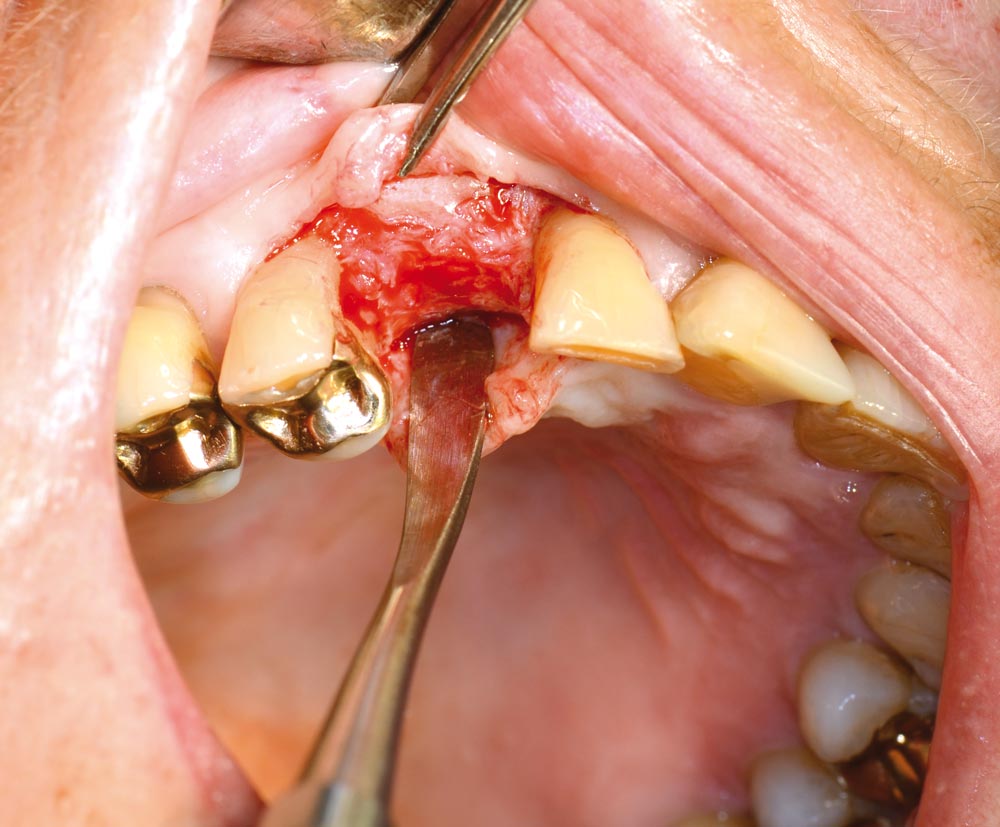

05/12 - Intraoperative situation

Block augmentation with maxgraft® in the maxilla - PD Dr. Dr. F. Kloss